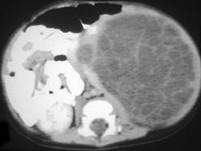

问题 男,5岁,左季肋部可触及一包块,请根据其影像,选择最可能的诊断 ( )

选项 A、左肾细胞癌 B、左肾多房性囊肿 C、左肾单纯性囊肿 D、左肾脓肿 E、左肾血管平滑肌脂肪瘤

答案 B